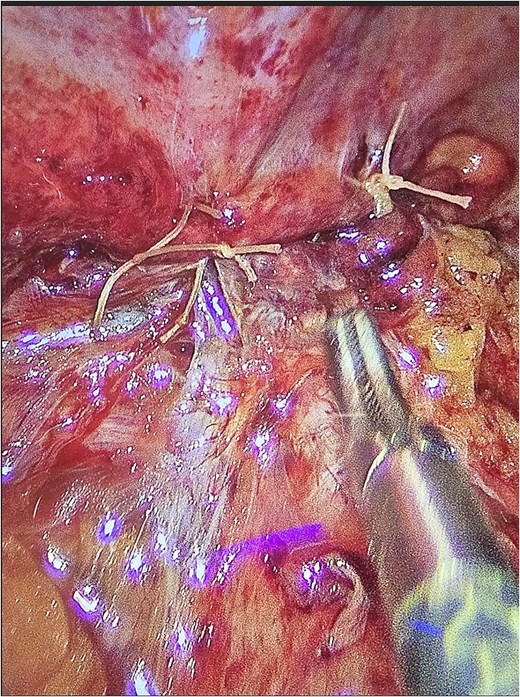

The patient underwent laparoscopic appendectomy with laparoscopic enterolysis. The appendix appeared inflamed, dilated, and gangrenous, with a perforation located 2 cm from the base. Notably, the appendix was not in a retrocecal position as initially suspected but was found to be herniating through a defect in the iliacus muscle (Fig. 3). The appendix was circumferentially freed from the hernia defect, which was identified as tracking cephalad between the iliacus muscle and the iliac bone. The hernia defect measured 2.5 cm and was primarily closed using two figure-of-eight 2–0 Vicryl sutures, leaving a small inferior opening to allow for drainage (Fig. 4). A 19 Fr Blake drain was placed in the right lower quadrant and paracolic gutter.

Intra-operative photos of appendix contained within iliacus hernia after appendix was divided. The arrows showcase the hernia with appendix. (A) Appendix, (B) mesoappendix after division, (C) cecum with staple line.